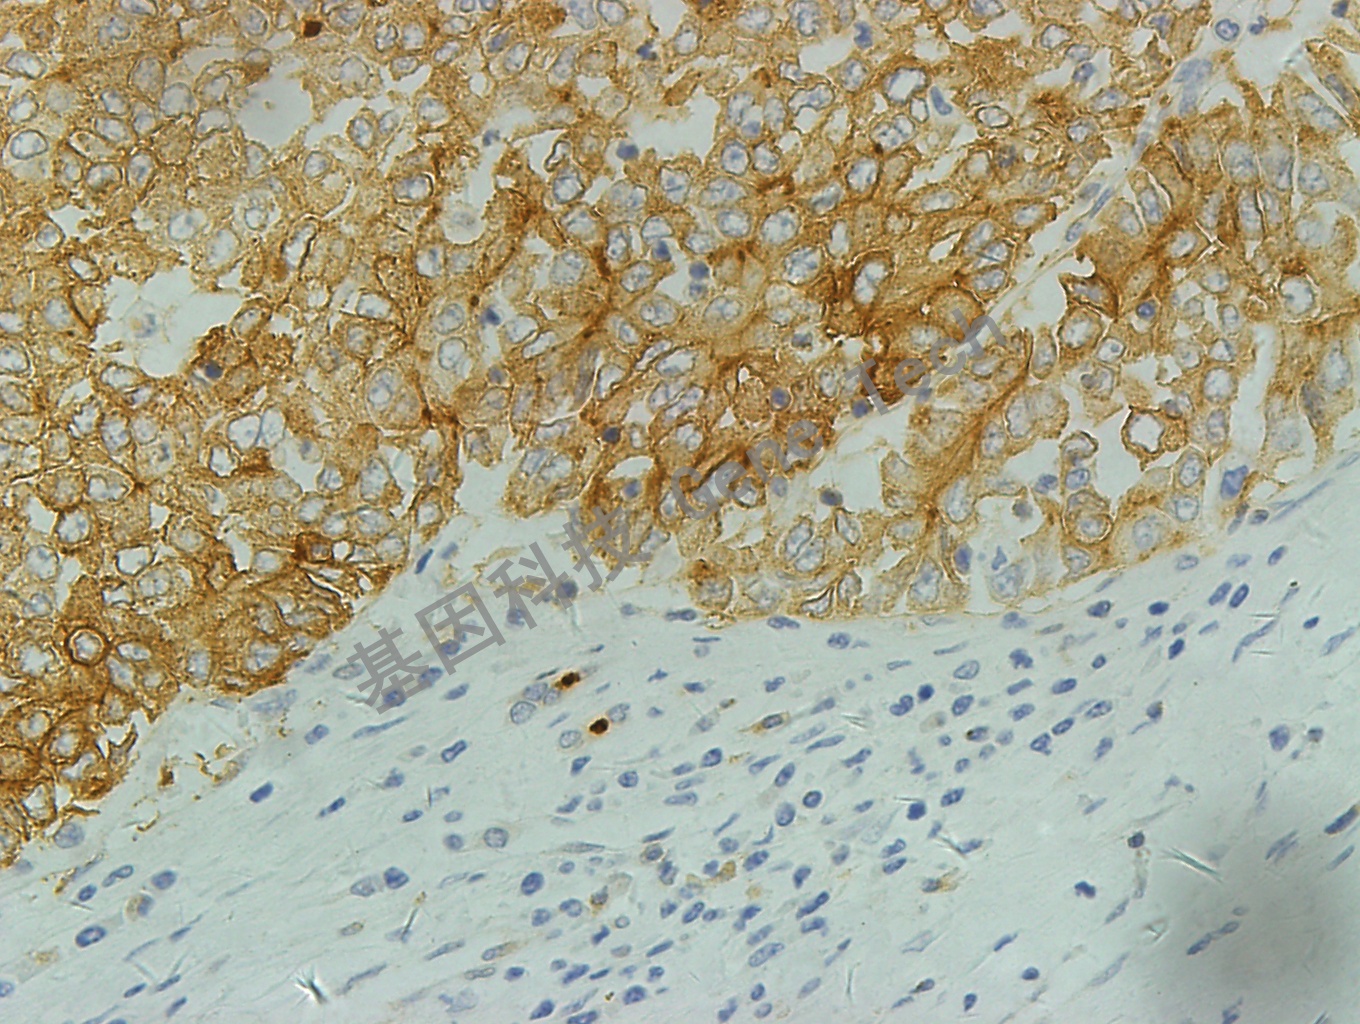

| 克隆號(hào):EP271 | 種屬:兔 | 適用染色系統(tǒng):GTvisionTM |

| 預(yù)處理:高pH熱修復(fù) | 陽(yáng)性部位:細(xì)胞膜 | 陽(yáng)性對(duì)照:肝 |

| 簡(jiǎn)介:P-Glycoprotein(P糖蛋白)是一種細(xì)胞膜蛋白,與多種親脂化療藥物的耐受性相關(guān)。該蛋白在多種正常組織的上皮轉(zhuǎn)運(yùn)中被發(fā)現(xiàn),包括肝、腎、結(jié)腸、腎上腺和腦。 P糖蛋白容易產(chǎn)生耐藥的藥物主要為長(zhǎng)春花堿類和阿霉素類,對(duì)腫瘤病人選擇化療方案和預(yù)后的判斷具有重要臨床意義。 | ||

| 肝癌石蠟切片,用 P-glycoprotein(GT2223)染色,細(xì)胞膜陽(yáng)性,DAB 顯色。 | ||